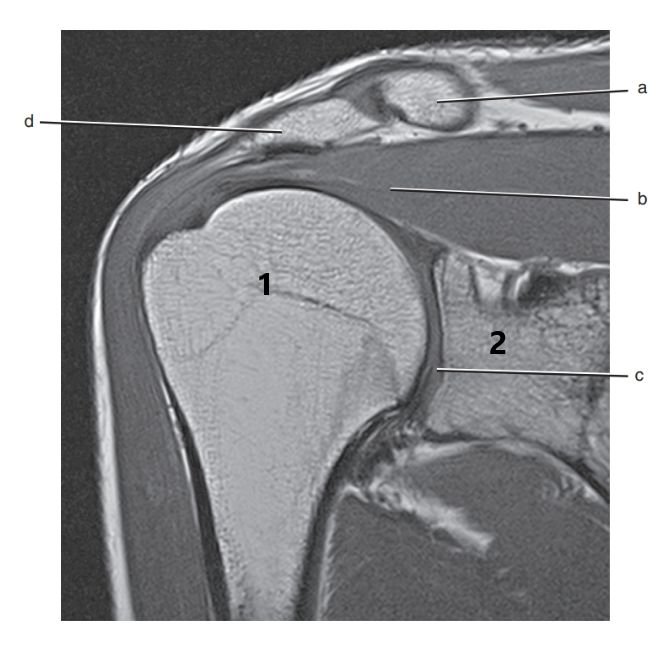

What is 1 ?

humeral head

What is d ?

glenoid labrum

supraspinatus tendon

acromion process

What is b ?

supraspinatus muscle

The structures that comprise the rotator cuff in the shoulder are:

I. Deltoid muscle

II. Subscapularis muscle and tendon

III. Infraspinatus muscle and tendon

IV. Teres minor muscle and tendon

V. Supraspinatus muscle and tendon

VI. Trapezius muscle and tendon

II,III,IV,V